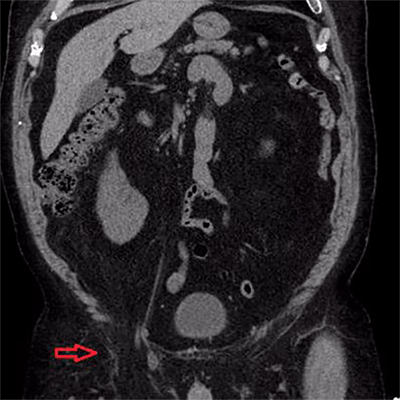

A 67-year-old male with history of hypertension, dyslipidemia, obesity, osteoarthritis, and chronic non-obstructing bilateral nephrolithiasis presented to the emergency department (ED) with a two day history of diffuse abdominal pain. He had associated polydipsia, polyuria and generalized fatigue. The patient reported the presence of chronic inguinal hernias bilaterally, which were asymptomatic and reducible for the last twenty years. During his ED evaluation he denied fever, chills, or changes in bowel habits. He did report hematuria and right sided flank pain with exertion, which he attributed to his known nephrolithiasis. The patient was afebrile and vital signs were within normal limits. Physical examination was remarkable for significant right scrotal swelling consisting of an incarcerated inguinal hernia. In addition, a reducible left inguinal hernia was present. Objective laboratory data included a complete blood cell count and liver function tests, which did not reveal any abnormalities. A renal function panel revealed an increase in the creatinine level to 1.6 mg/dL from his baseline of 0.9 mg/dL that had been constant for the past year. Given his history of nephrolithiasis with acute renal failure, the ED staff along with the medicine team decided to perform a non-contrast computed tomography (CT) to evaluate for acute urinary tract obstruction secondary to stones. The CT scan revealed the following findings: Bilateral fat-containing inguinal hernias, with the right side being larger than the left side, and interestingly, containing the right ureter, which was mildly dilated and extended into the hernia sac (Figure 1). Additionally, retroperitoneal and extraperitoneal fat extended also into the right inguinal hernia (Figure 2). The ureter distal to the sac was decompressed at the level of the internal ring, which raised the concern for incarceration of this portion of the ureter (Figure 3). Finally, the CT also revealed bilateral non-obstructing renal and bladder calculi with significant right sided hydronephrosis that was likely due to the incarcerated ureter (Figure 4).

Figure 1. Axial view of CT showing bilateral fat-containing inguinal hernias with the right side containing the ureter.

Figure 2. Coronal view of same study showing retroperitoneal and extraperitoneal fat extending into the right inguinal hernia.